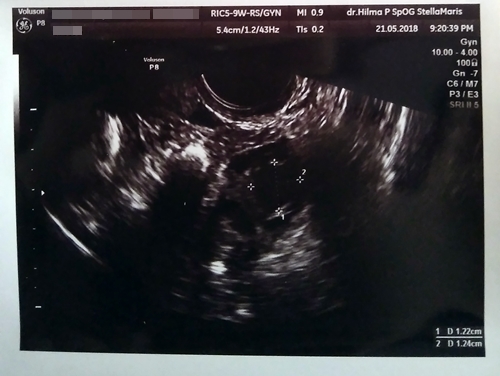

Gambar Usg Sel Telur Matang

BEGINI GAMBAR SEL TELUR YANG SUBUR… - dr Yudhistya SpOG | Facebook Story of My Journey: TTC Journey #2 USG Folikel dan Hasil Analisa Sperma Aku dan PCOS (Hasil USG Trans Vaginal) - JalanSenja.com Cerita Promil 4 - Polycystic ovary (PCO) - Fika Putri Cerita Promil 2 - USG Transvaginal dan Tes Sperma - Fika Putri Semua Akan Terjawab di Waktu yang Tepat - kumparan.com Promil Story : MIMPI BURUK ITU BERNAMA PCOs - The Arsalan Family Journal Penting Dilakukan Wanita, Ketahui Sel Telur Dalam Tubuhmu Jangan Sampai “Mandul” Karena Kehabisan Program Hamil di Dokter Lusiana Irene, SpOG Jogja Manusia sedikit tahu..sel telur kecil tidak mungkin hamil | Dr Suryo, SpOG - Kesehatan Reproduksi C e r i t a C i k i: Sel Telur Kecil-Kecil EFEK PENYUBUR Pada wanita normalnya sel… - dr Yudhistya SpOG | Facebook Ikhtiar yang ke dua – Part 2 (H6-H11) – Bread and Butter Letter Promil Step 4 – Baby Journey PCOS adalah… | Kisah Ibuknda (pakai ‘k’) :D Room | ‘Aisyah Tsurayya Inart’s Story - Yah, Saya Akhirnya Hamil - I’m 1 In 10: My PCOS Story Kisah Perjuangan Terbaru Tya Ariestya Saat Jalani Program IVF | Popmama.com story of my lyfe: pejuang keturunan Nikita Mirzani Bagikan Hasil USG Bayi Kembar, Dapatkah Gen Kembar Diturunkan? - Semua Halaman - Intisari lihat hasil USG tranvaginalku wktu bulan Januari 2013 apa itu PCO? - IbuHamil.com Cerita Promil 4 - Polycystic ovary (PCO) - Fika Putri aq PCO bund, ada yg bisa bantu baca hasil USG intravagina q??? - IbuHamil.com Hasil USG Sel Telur Yang Subur - YouTube Pengalaman Bayi Tabung/ IVF (Part II) Update with Pict! | honeymenulis’s Blog Inart’s Story - Yah, Saya Akhirnya Hamil - Story of My Journey: June 2017 Ingin Terhindar dari Kista? Jauhi 4 Jenis Makanan Enak Ini Sekarang! - Semua Halaman - Grid Health Program Hamil Bulan ke-1 : PCOS Survivor | Lanalouie Embrio 3 cm berapa minggu. minggu: bayi Anda sebesar tongkol jagung BEGINI GAMBAR RAHIM YANG SUBUR… - dr Yudhistya SpOG | Facebook PCOS | medicalstudentnotes USG Transvaginal: Penjelasan, Prosedur & Manfaat (Lengkap) | Friso BILIK SONOGRAFER : Kista Ovarium Kontrol H+10 (Cek Perkembangan Sel Telur) Istilah kehamilan dipertimbangkan dengan USG. Kehamilan kebidanan dan embrio Selamat Pagi Senin Ayah Bunda. Semoga… - Dokterkandungan. id | Facebook My First USG | Story of Us Menuju Hamil – Part 2 of 3 – Edward Suhadi Apa itu PCOS? Kenapa Sulit Hamil? | Sunshine of My Life Setiap Ibu Hamil Harus Tahu, Kapan Harus Melakukan USG lewat Vagina? - Semua Halaman - Nakita Program Hamil di Dokter Lusiana Irene, SpOG Jogja Saat Sel Telur Berukuran Kecil dan Sulit Dibuahi - Health Liputan6.com Kabar Gembira, Ini Tanda Awal Sel Telur Berhasil Dibuahi oleh Sperma | Popmama.com 101+ Gambar Cek Sel Telur Paling Hist - Gambar Pixabay Kontrol H+12 (Mendebarkan, apakah sel telurnya tetap berkembang?) Program Kehamilan Balasan dari Saya Penderita PCOS, Saya Berhasil Hamil | KASKUS Pembekuan Sel Telur: Fungsi, Prosedur, dan Komplikasi INGIN HAMIL – Siklus Ovarium dan Tanda-Gejala Wanita Subur | JuliantoWitjaksono.com 6 Fakta Mengejutkan Tentang Sel Telur Wanita - YouTube Pengalaman Hamil Kembar - The Urban Mama Maimuns — PCOS? Deal with it! Berapa Sisa Sel Telur di Tubuh? Bisa Dicari Tahu | Parenting.Dream.co.id PCOS Polycystic Ovary Syndrom Apakah… - Komunitas Impian Bunda | Facebook Persiapan Hamil (4) – jurnal Ammi Wanita Hasilkan 2 Sel Telur dalam Masa Ovulasi, Bisakah Terjadi? Promil Story : MIMPI BURUK ITU BERNAMA PCOs - The Arsalan Family Journal My journey to motherhood: HSG, Tes Sperma, hingga PCO Polikistik Ovarium (PCOS): Haid sering tidak datang, Berkumis, Berjerawat, Ingin hamil sulit | Dr Suryo, SpOG - Kesehatan Reproduksi PCOS dan Metformin. Sohib karib! – Cerita Bumi Blighted Ovum | ~cahaya kebaikan~ Cerita Pengalaman Kehamilan Pertama dan Persiapan Melahirkan Anak Pertama - For The Love of Foods and Beauty Masih banyak yg belum tau.. INSEMINASI… - Bayi Tabung PMC Pekanbaru Cerita Program Hamil dengan Dokter Enny Sp.OG di Yogyakarta ~ Land of Jenganten Semua Akan Terjawab di Waktu yang Tepat - kumparan.com Fika Putri Berbagi Tips: Cara Mengetahui Masa Subur Wanita Berdasar Penghitungan serta Ciri-Cirinya - Garda Remaja GAGAL OVULASI?? SERING TERJADI PADA… - Konsultasi Promil Cepat Hamil dan Alami | Facebook Yosevina Issabela prosespersalinan Instagram posts (photos and videos) - Picuki.com Apa sebetulnya bayi tabung dan bagaimana proses menjalaninya? – Bayi Tabung Penang Di minggu kebidanan mana embrio terlihat. Minggu berapa embrio terlihat pada USG? Apakah prosedurnya aman pada tahap pembentukan anak PCOS itu Variable dan Sangat Rumit Prosedur Bayi Tabung: Sebelum dan Sesudah Mengikutinya - Smarter Health Mengenal Kehamilan Kosong atau Blighted Ovum (BO) - Kompasiana.com Cerita Promil, Perjalanan menuju kehamilan (long story short, I finally got pregnant) - Nyonyah Intan Sindrom Ovarium Polikistik (PCOS) 4D Gallery | Dr Suryo, SpOG - Kesehatan Reproduksi Kapan USG direncanakan selama kehamilan. Apakah saya perlu mempersiapkan prosedur? Keadaan organ reproduksi wanita Irish Bella Hamil Anak Kembar, Sang Ibunda Tak Sangka Bakal Punya 2 Cucu - Halaman all - Tribun Batam Lapsus Kista Ovarii - Apriamalia - [PDF Document] Success story – GLADIOOL IVF RS Indosehat Solo, Jl Solo Sragen Km 11, Kebakramat, Karangdawa (2020) Saya Penderita PCOS, Saya Berhasil Hamil | KASKUS September 2014 - Pipit Widya Aku dan PCOS (Hasil USG Trans Vaginal) - JalanSenja.com Pengalaman PCOS-ku yang Berhasil Hamil Alami - kumparan.com Apakah USG mempengaruhi kehamilan. Bagaimana ultrasound mempengaruhi embrio? Ultrasonografi dilakukan hanya atas kesaksian dokter atau mungkin atas permintaan ibu BAB III - [DOCX Document] Kista Ovarium. - ppt download Biaya USG 3 & 4 Dimensi di Karawang - Perawatan Kesehatan Cerita Pengalaman Kehamilan Pertama dan Persiapan Melahirkan Anak Pertama - For The Love of Foods and Beauty Wanita Punya 400 Sel Telur Setiap Menstruasi, Kenapa Susah Hamil? - Semua Halaman - Nakita Tragis Si Ibu Hamil Dibunuh, Bayi di Dalam Kandungan Dicuri - Halaman all - Warta Kota Perlukah USG Transvaginal saat Program Hamil? | Popmama.com 13 Tanda - tanda Kehamilan Awal yang Bisa Dipercayai - Mamapapa.id Melahirkan bayi kembar pada minggu-minggu kehamilan. Dapatkah dokter tidak melihat bayi kembar dengan USG: diagnosis dini kehamilan ganda PROSES DAN BIAYA INSEMINASI 1. USG USG… - dr Yudhistya SpOG | Facebook